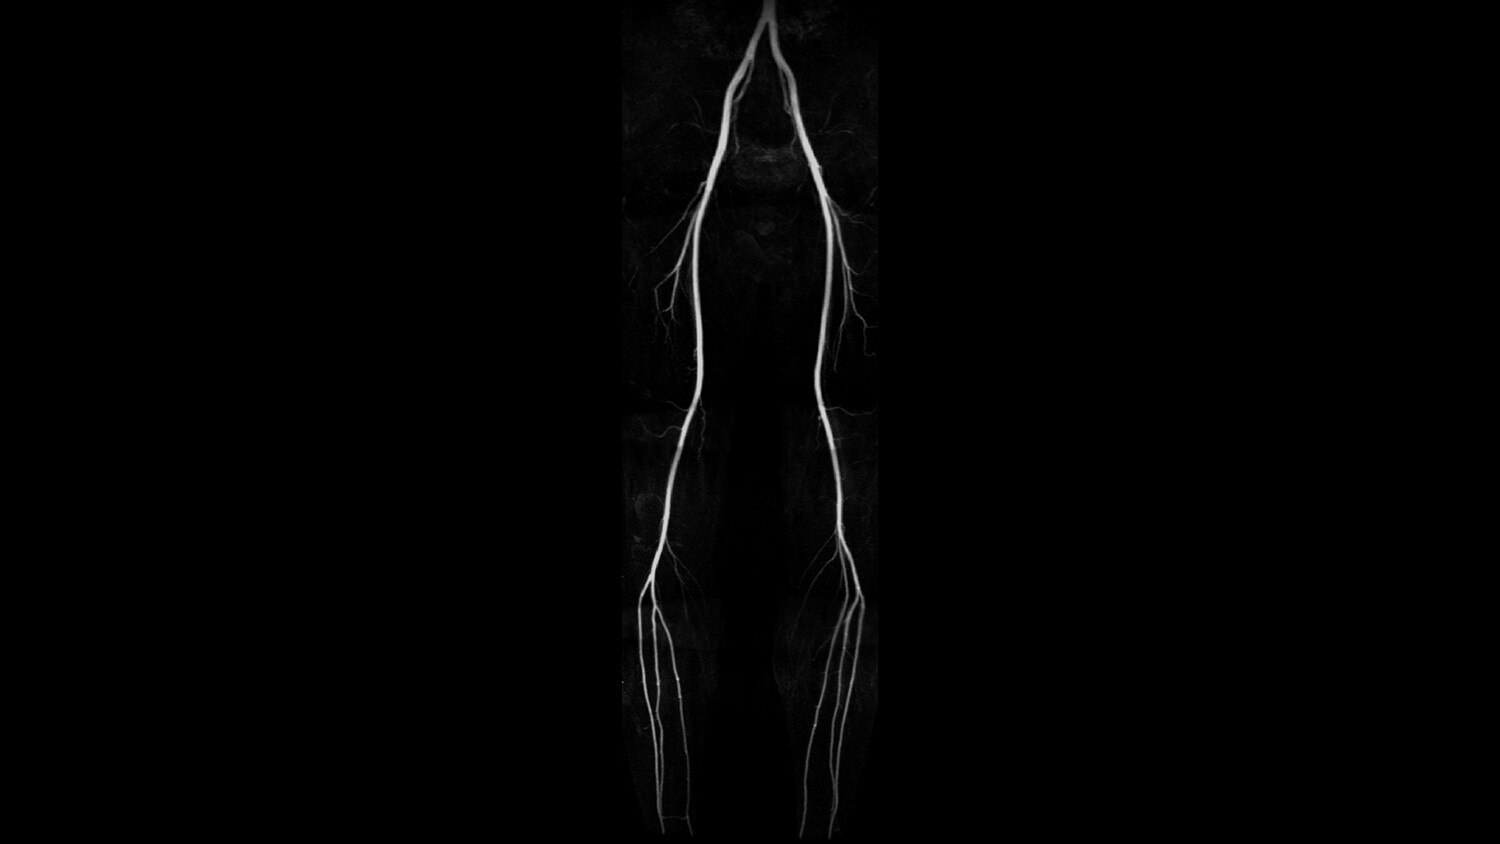

GEM Peripheral/Vascular Array - A high-density PV / lower extremity array that facilitates imaging of the thighs and lower legs with parallel imaging in all 3 planes. The coil incorporates an innovative self-supporting hinge design between the upper and lower elements to accommodate patients of various sizes with simplified set-up.

Its full 3.0T magnet and 70 cm bore work together to generate extraordinary image quality without compromises. The result for clinicians is new levels of diagnostic performance.

A large usable field of view is needed to properly image off-center anatomy such as a shoulder or hip. So the Discovery* MR750w features a 70 cm flared, open bore design with a large 50 x 50 x 50 cm field of view.